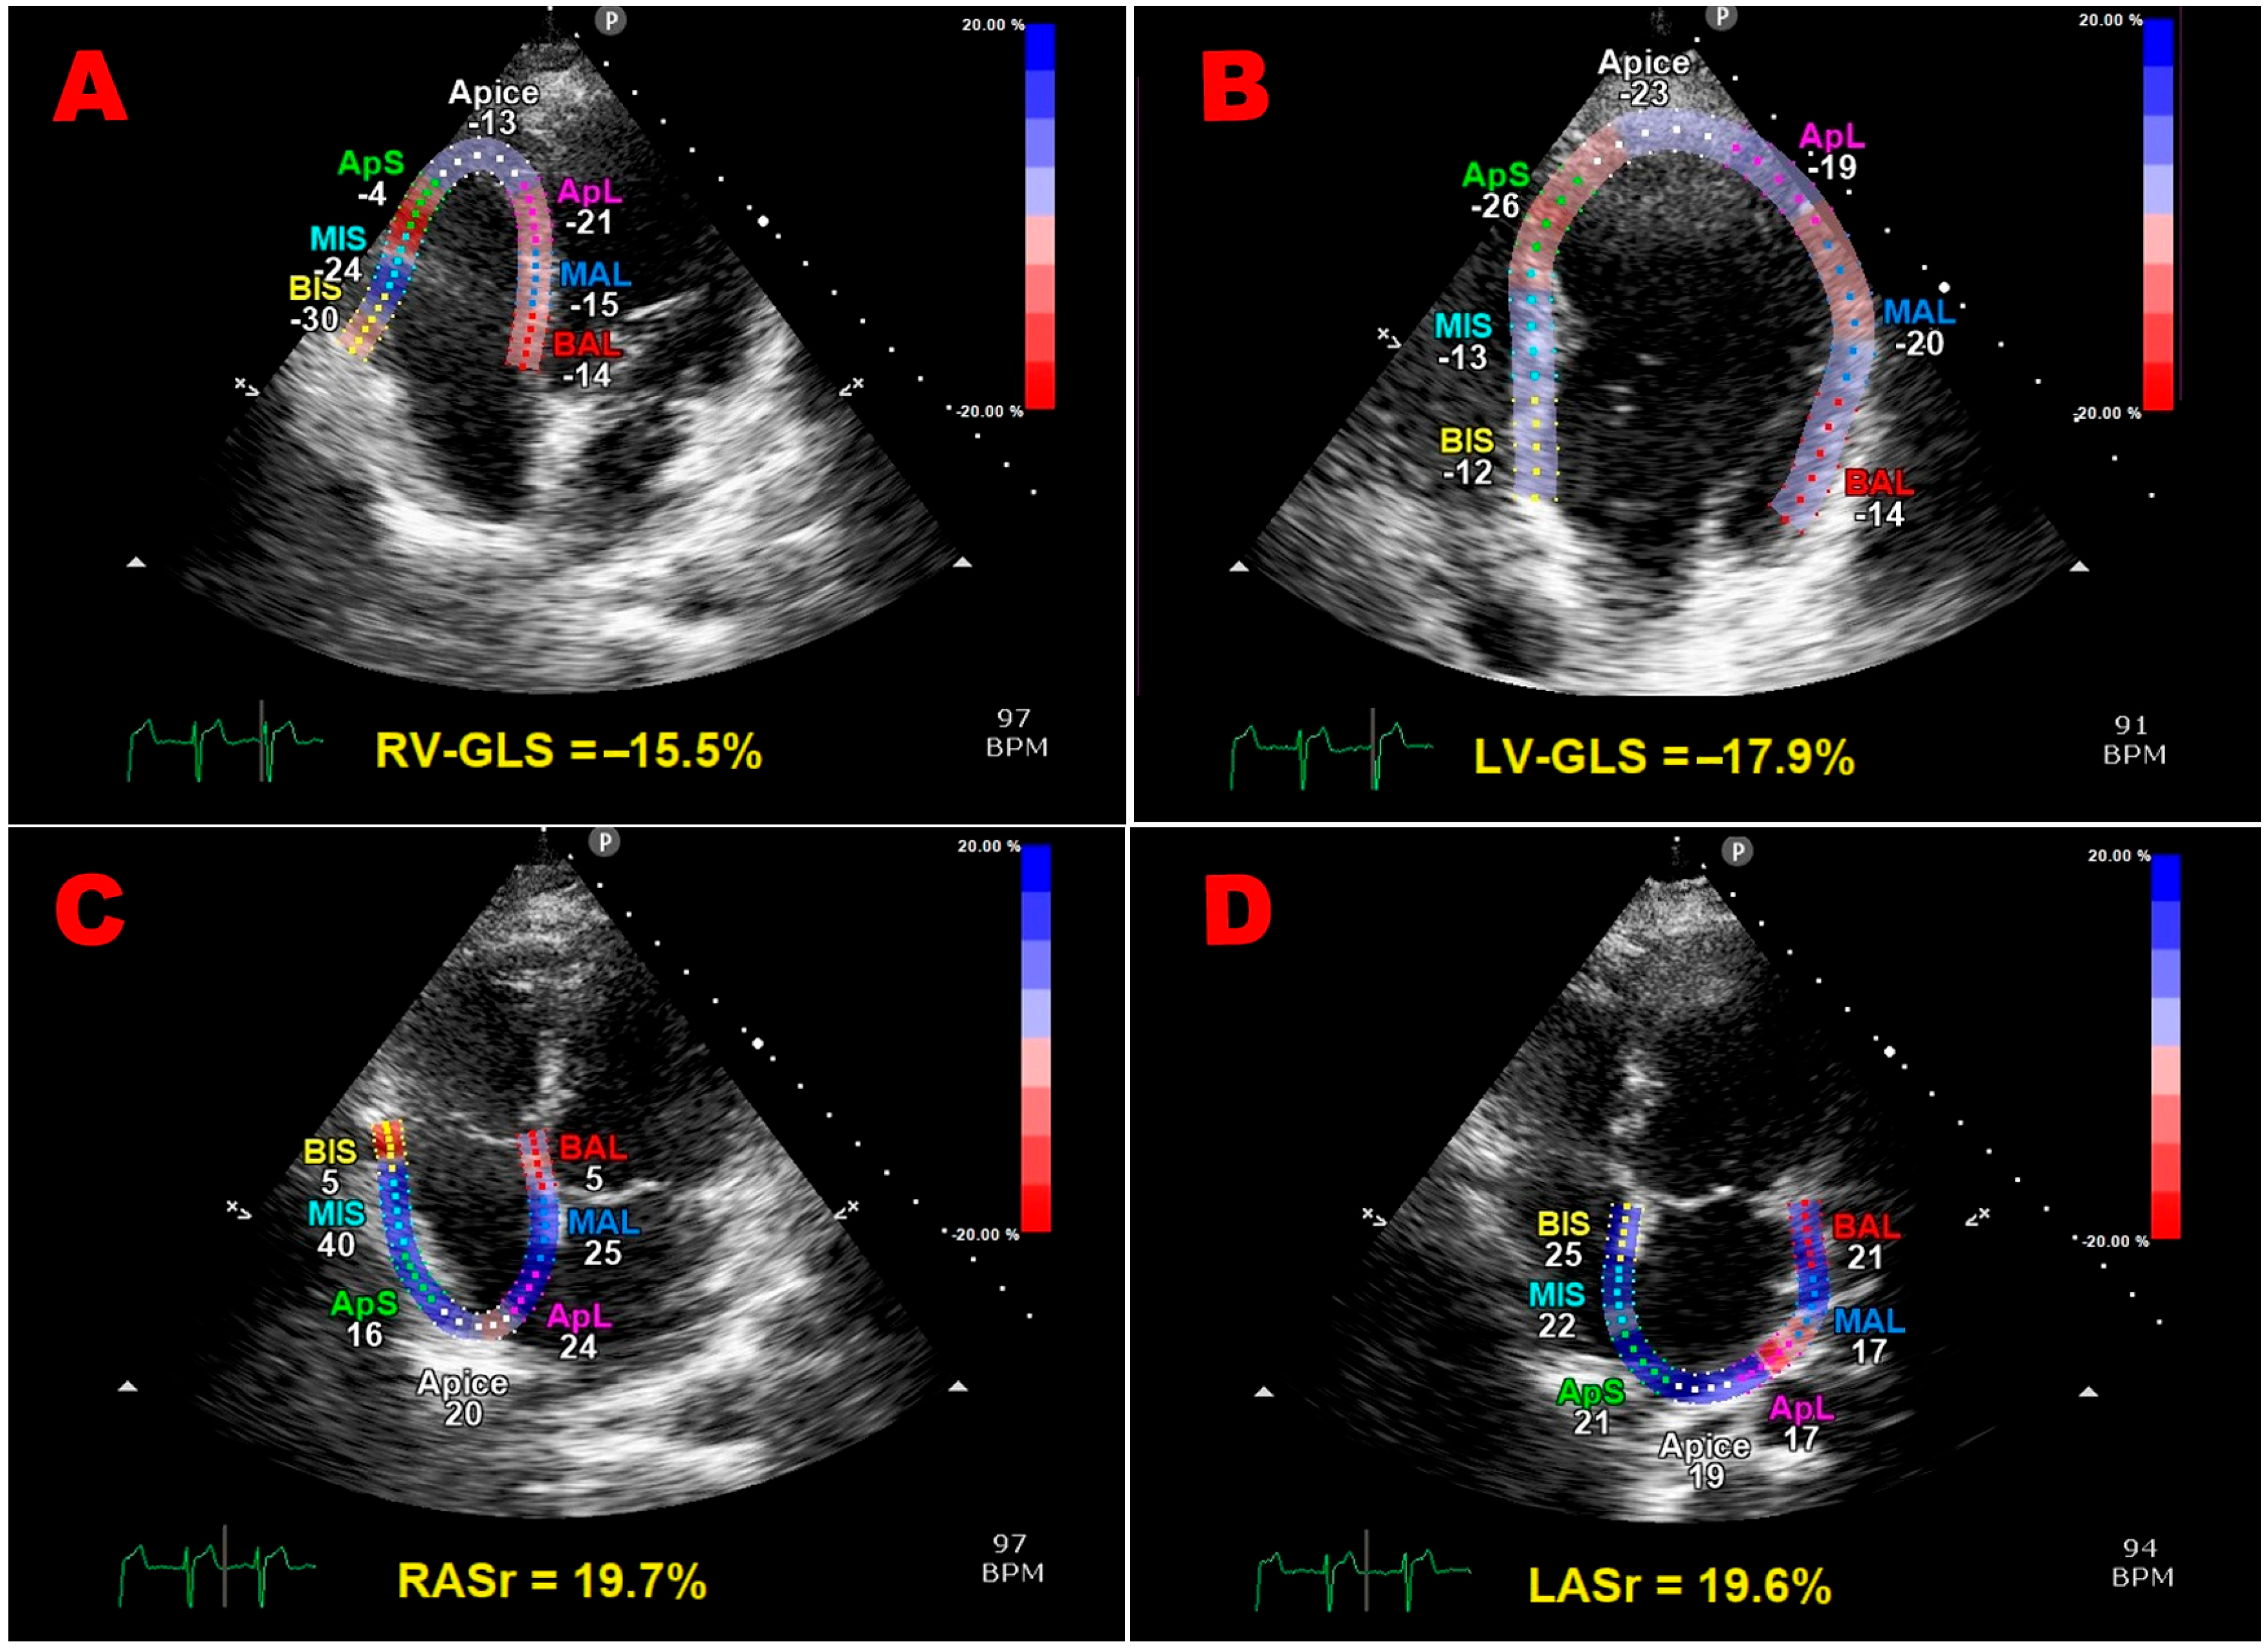

| STE VARIABLES | pGDM Women (n = 32) | Controls (n = 30) | p-Value |

|---|---|---|---|

| LV-GLS (%) | 19.5 ± 2.6 | 22.3 ± 2.3 | <0.001 |

| LV-GLSR (s−1) | 1.1 ± 0.1 | 1.2 ± 0.1 | <0.001 |

| LV-GCS (%) | 22.8 ± 4.48 | 26.7 ± 4.4 | 0.001 |

| LV-GCSR (s−1) | 1.6 ± 0.3 | 1.7 ± 0.2 | 0.13 |

| LAScd (%) | 29.8 ± 8.9 | 36.3 ± 7.7 | 0.003 |

| LASct (%) | 7.3 ± 4.2 | 9.5 ± 4.1 | 0.04 |

| LASr (%) | 37.1 ± 9.2 | 45.7 ± 8.0 | <0.001 |

| LASr/E/e’ | 4.4 ± 1.8 | 9.5 ± 3.2 | <0.001 |

| LA-GSR (s−1) | 1.9 ± 0.5 | 2.3 ± 0.5 | 0.002 |

| LA-GSRE (s−1) | 2.4 ± 0.7 | 3.1 ± 0.8 | <0.001 |

| LA-GSRL (s−1) | 2.5 ± 0.6 | 2.8 ± 0.5 | 0.04 |

| RV-FWLS (%) | 19.9 ± 3.8 | 22.0 ± 3.5 | 0.03 |

| RV-GLS (%) | 18.8 ± 3.9 | 20.9 ± 3.4 | 0.03 |

| RV-GLSR (s−1) | 1.1 ± 0.2 | 1.3 ± 0.2 | <0.001 |

| RAScd (%) | 26.3 ± 11.7 | 34.6 ± 10.1 | 0.004 |

| RASct (%) | 6.1 ± 4.46 | 7.5 ± 5.4 | 0.27 |

| RASr (%) | 32.4 ± 11.0 | 42.1 ± 9.9 | <0.001 |

| RA-GSR (s−1) | 2.0 ± 0.9 | 2.5 ± 0.6 | 0.01 |

| RA-GSRE (s−1) | 1.9 ± 0.6 | 2.3 ± 0.7 | 0.02 |

| RA-GSRL (s−1) | 2.0 ± 0.6 | 2.5 ± 0.8 | 0.007 |